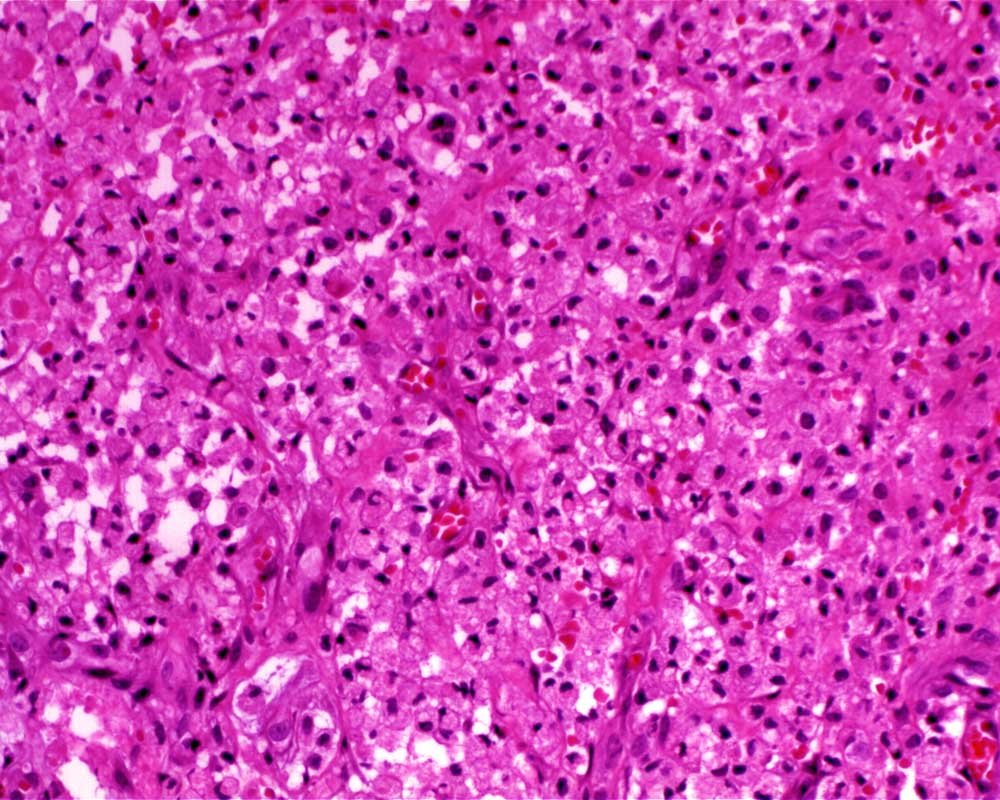

Case: FemurLesion

Final Diagnosis: